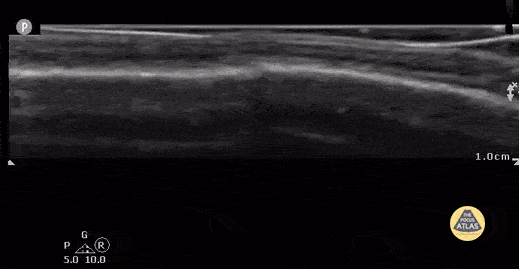

same 4 week old with non-displaced parietal fracture after compression and displacement of fluid from the water filled glove. (Case Series 2/2) Contributor: Antonio Riera, MD